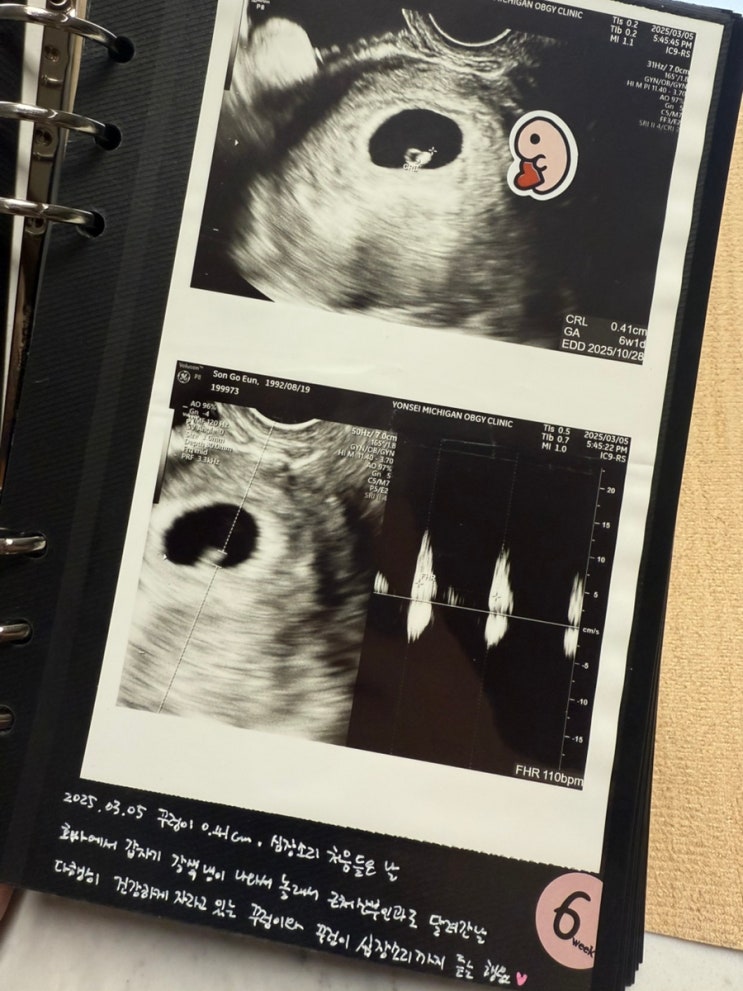

임신 6-7주 차, 심장소리, 갈색냉, 부모님 임밍아웃 이벤트

아기집과 난황을 보는 것이 보통 5주 차~ 좀 늦으면 6주 차이고, 그다음 6~7주 차 정도에는 아기 심장소리...